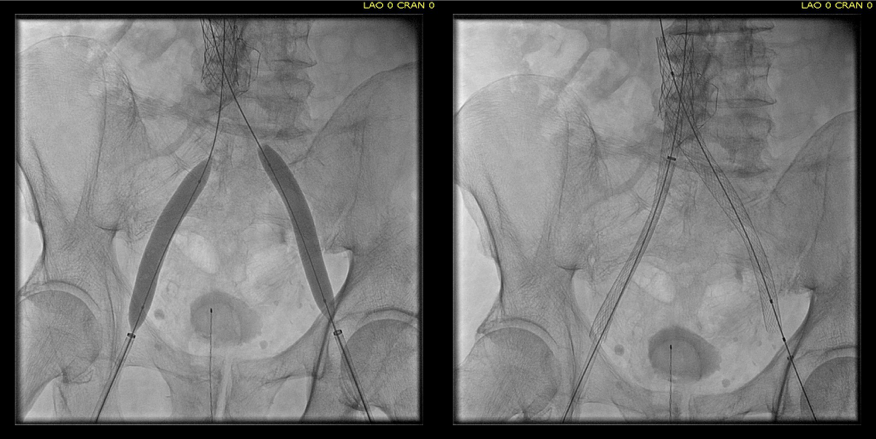

Once wire access is done, ballooning across the filter is done from both sides. A large sheath is them delivered across the IVC filter. Finally, a Palmaz stent mounted on a large balloon is delivered and deployed. I chose to do this from the right access, and retracted the wire on the left -something done with some trepidation because of the great difficulty gaining this access, but with with prior balloon dilatation, reaccess is made easier. Also, plan B would be reaccess from above.

intervention fig 4.png

After balloon dilatation of occlusion typically to 8mm from both sides, a sheath placed and Palmaz stent deployed across filter on a large 24mm balloon

When this is accomplished, the left sided wire is reaccessed across this stent. This is the venous side analogue to gate access in EVAR (below).

intervention fig 5.png

Reaccess of the left iliac venous wire across Palmaz stent